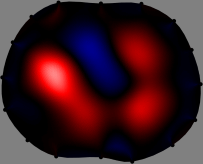

Figs. 3 and 4 compare the performance of the proposed FER method in (20) with the standard regularized least-squares method ((19) when is the identity matrix). The regularization parameter of the standard method was heuristically chosen for its best performance, and the parameter of the FER method was set to be one of three different values . The injection current was 1 mA at 100 kHz, and the frame rate was 9 frames per second. The reference frame at was obtained from the maximum expiration state. The measured data, , represent the voltage differences between each time and . The blue regions, which denote where conductivity decreased by inhaled air, increased during inspiration and decreased during expiration. The FER method with was clearly more robust than the standard method that produced more artifacts originated from the inversion process.